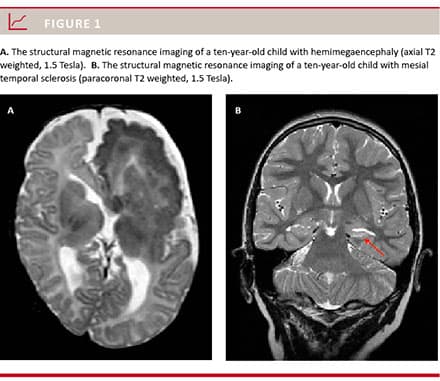

The three most frequent MRI diagnoses were cortical dysplasia (24.2%), mesial temporal sclerosis (MTS; 17.9%) and tumour/dysembryoplastic neuroepithelial tumour (DNET; 13.7%). Changes over time were seen with an increasing percentage of patients with cortical dysplasia and MTS and a decreasing number of patients with tumours (Table 2). Patients in Engel class I were unequally distributed according to the MRI diagnoses. MTS had the best result for Engel class I (94%) and reoperated children were included in the analysis. Among children with normal MRI, only 25% were classified as Engel I. Figure 1 illustrates the MRI findings in a child with hemimegaencephaly and a child with MTS.

In the article Danish experience with paediatric epilepsy by von Celsing Underbjerg et al. Dan Med J 2015;62(12)A5164, the text in Figure 1 has been corrected on January 18 2016.